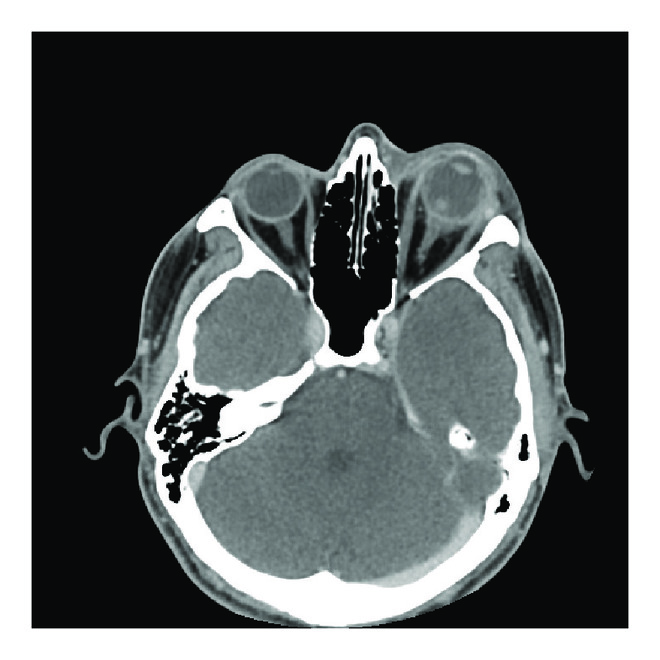

A repeat CT of the orbits identified retrobulbar fat stranding and thickening of the posterior sclera (Figure 1(b)). There was also now a focus of soft tissue density in the vitreous (Figure 1(c)). At this time consultation with a retina physician was obtained and the option of tap and inject or vitrectomy with intravitreal antibiotics was discussed. Tap and inject or vitrectomy was not performed as it was clear that this was a panophthalmitis with severe corneal melting and NLP vision.